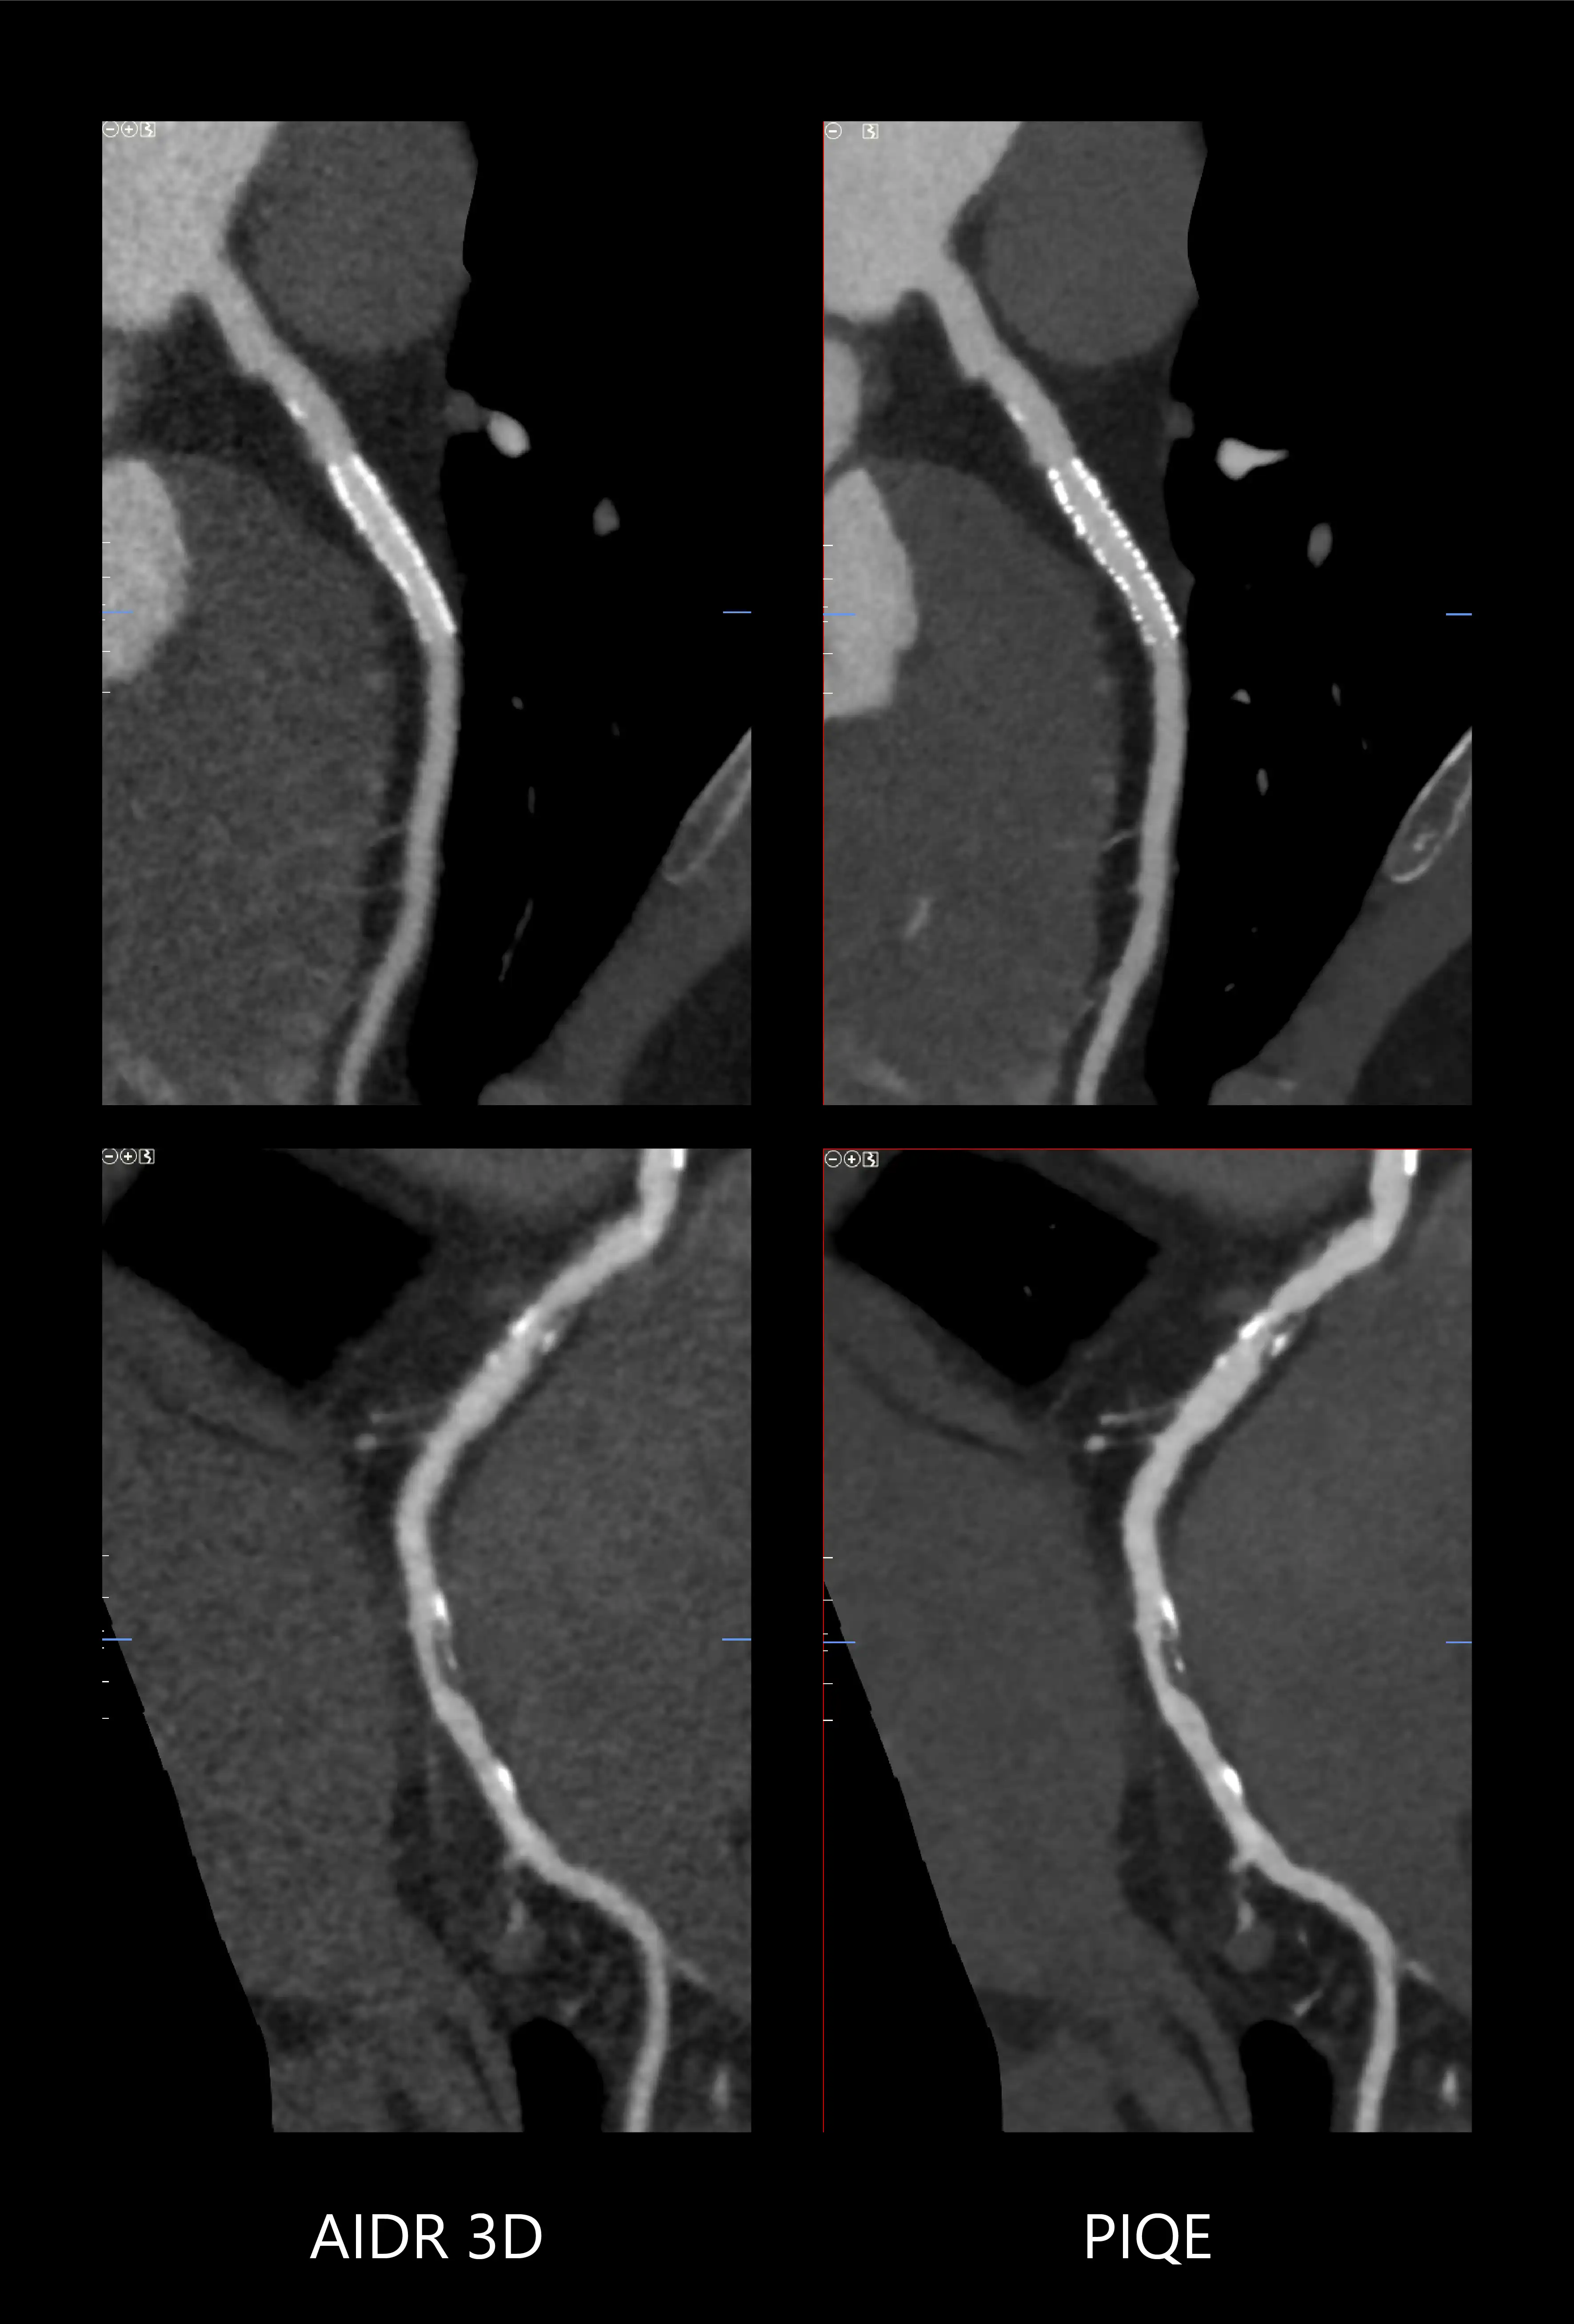

PIQE provides improved spatial resolution and 45% reduced noise* for improved in-stent visualization with clear depiction of vessel lumen to evaluate neointimal hyperplasia and in-stent restenosis. The high contrast to noise properties of PIQE exams also provide better evaluation in heavily calcified coronary arteries with no loss of low contrast detectability* – and these benefits are provided without any additional dose.

*Compared to AIDR 3D

Courtesy of Dr. Marcus Chen, NHLBI, National Institutes of Health, USA